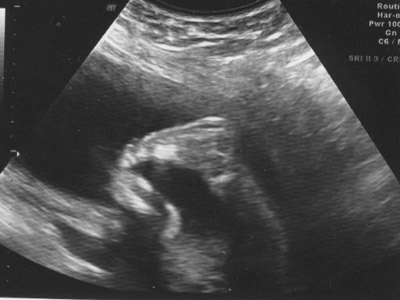

They started with the general level II ultrasound showing different body parts and organs of the baby. Time was taken to measure things like the amount of amniotic fluid, the size of the head and stomach, and the general size of the baby. Everything looked as it should even down to measuring within one day of my due date. The baby appears to weigh about 1 lb. 3 oz. by their measurements. The only thing that was remotely odd was the position the baby was in, though that won't present a problem unless the baby decides to try to be born this way. Basically he/she was breech with one leg held all the way up to the head. Here are some pictures:

An arm and hand: